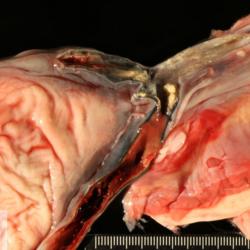

Etiquetes: N-133/15 4 total Equine Specie: Equine Organ: Muscle Lesion: Abscess Lesion modifier: - Disease: Septicemia Files/Expedient: N-133/15 Position: 252 (1 views) Equine Specie: Equine Organ: Joint Lesion: Arthritis Lesion modifier: Arthritis - Fibrinous-purulent Disease: Septicemia Files/Expedient: N-133/15 Not viewed Equine Specie: Equine Organ: Blood vessel Lesion: Omphalophlebitis Lesion modifier: Omphalophlebitis - Fibrinous-purulent Disease: Septicemia Files/Expedient: N-133/15 Not viewed Equine Specie: Equine Organ: Blood vessel Lesion: Omphalophlebitis Lesion modifier: Omphalophlebitis - Fibrinous-purulent Disease: Septicemia Files/Expedient: N-133/15 Not viewed Títol Select...Avian (Exotic) (110)Avian (Poultry) (76)Bovine (317)Canine (935)Caprine (47)Equine (257)Feline (326)Ferret (19)General (127)Marine mammal (22)Non-human primate (20)Ovine (328)Porcine (379)Rabbit (61)Reptile (38)Rodent (28)Wildlife (91) Format Select...- (60)Abomasum (37)Adrenal gland (10)Blood (7)Blood vessel (50)Body as a whole (19)Bone (57)Bone marrow (21)Brain (93)Cloaca (1)Diaphragm (2)Ear (5)Esophagus (39)Eye (16)Fetus (12)Gallbladder (23)Gizzard (2)Heart (265)Intestine (356)Joint (32)Kidney (443)Larynx (5)Liver (326)Lung (264)Lymph node (91)Mammary gland (10)Mediastinum (1)Muscle (22)Nasal cavity (22)Nerve (7)Omasum (5)Oral cavity (63)Ovary (14)Oviduct (8)Pancreas (7)Parathyroid (5)Penis (10)Peritoneum (65)Pharynx (9)Pituitary gland (6)Placenta (7)Prostate (8)Proventriculus (3)Reticulum (1)Rumen (28)Sinus (7)Skin (181)Spinal cord (15)Spleen (105)Stomach (125)Teeth (1)Testicle (11)Thoracic cavity (31)Thymus (13)Thyroid gland (5)Tongue (32)Tonsils (11)Trachea (11)Urethra (5)Urinay bladder (61)Uterus (27)Vagina (1)Vulva (1)Yolk sac (1) Cobertura Select...- (152)Abomasitis (26)Abscess (27)Acidosis (1)Adenocarcinoma (20)Adenoma (9)Aerosacculitis (6)Agenesis (1)Agnathia (1)Alopecia (7)Amyloidosis (12)Aneurysm (6)Angiectasis (1)Anthracosis (1)Arteritis (11)Arthritis (15)Arthrogryposis (6)Artifact (4)Ascites (13)Atelectasis (8)Atherosclerosis (5)Atresia (1)Atrial septal defect (2)Atrophy (10)Autolysis (7)Bronchitis (6)Bronchopneumonia (26)Cachexia (2)Carcinoma (103)Cardiomyopathy (19)Cellulitis (2)Chemodectoma (4)Cholangiohepatitis (4)Cholangitis (19)Cholecystitis (4)Cholestasis (5)Chondrodysplasia (2)Chondrosarcoma (2)Chronic passive congestion (13)Chylothorax (2)Cirrhosis (6)Coelomitis (3)Coenurus cerebralis (4)Colitis (40)Congestion (17)Conjunctivitis (5)Coronitis (3)Cryptorchidism (3)Cyst (25)Cystitis (24)Dermatitis (69)Diaphragmatic hernia (4)Dilation (28)Discospondylitis (1)Disseminated intravascular coagulation (7)Dyschondroplasia (1)Dysplasia (29)Ectopia cordis (1)Ectopic ureter (1)Edema (55)Emphysema (5)Encephalitis (5)Endocardiosis (14)Endocarditis (26)Endometritis (5)Enteritis (118)Enterolith (6)Epulis (3)Esophagitis (14)Fasciitis (1)Fibrosis (7)Fibrous osteodystrophy (8)Fistula (1)Folliculitis (3)Fracture (2)Gastritis (34)Gingivitis (5)Glioma (8)Glomerulonephritis (21)Glossitis (25)Glycogenosis (1)Gout (8)Granuloma (2)Granulosa cell tumor (4)Hemangioma (9)Hemangiosarcoma (46)Hematoma (8)Hemoglobinuria (2)Hemopericardium (12)Hemoperitoneum (2)Hemorrhage (100)Hemosiderosis (7)Hemothorax (2)Hepatitis (78)Hernia (11)Histiocytosis (3)Hydatid cyst (11)Hydrocephalus (9)Hydrometra (1)Hydronephrosis (22)Hydropericardium (6)Hydrothorax (3)Hydroureter (5)Hyperkeratosis (8)Hyperostosis (4)Hyperplasia (37)Hypertrophy (9)Hypopigmentation (1)Hypoplasia (7)Hypopyon (1)Impaction (6)Infarction (63)Insulinoma (6)Intussusception (5)Jaundice (17)Laminitis (2)Laryngitis (2)Leiomyoma (5)Leukemia (13)Lipidosis (36)Lipoma (7)Lymphadenitis (45)Lymphadenopathy (7)Lymphangiectasia (6)Lymphangitis (5)Lymphoma (221)Malacia (11)Malignant melanoma (15)Mast cell tumor (11)Mastitis (8)Megaesophagus (2)Melanosis (3)Melena (4)Meningioma (6)Meningitis (6)Meningocele (2)Meningoencephalitis (5)Mesothelioma (5)Methemoglobinemia (2)Mineralization (10)Mucocele (5)Mucometra (1)Multilobular bone tumor (1)Mummification (3)Myelofibrosis (1)Myocarditis (4)Myositis (5)Necrosis (81)Nephritis (113)Nephroblastoma (6)Nephrosclerosis (1)Nephrosis (14)Neuritis (1)Obstruction (13)Omasitis (4)Omphalitis (1)Omphalophlebitis (7)Orchitis (4)Osteoarthrosis (5)Osteomyelitis (9)Otitis (2)Palatoschisis (3)Pancreatitis (3)Panniculitis (3)Papilloma (7)Parakeratosis (14)Patent ductus arteriosus (6)Peliosis hepatis (1)Perforation (17)Pericarditis (35)Peritonitis (39)Persistent right aortic arch (1)Pharyngitis (2)Pheochromocytoma (2)Phlebitis (2)Placentitis (6)Pleuritis (21)Pleuropneumonia (24)Pneumonia (109)Pneumothorax (3)Polycystosis (14)Polyp (5)Polyserositis (6)Posthitis (1)Proctitis (4)Prolapse (3)Prostatitis (3)Proventriculitis (1)Pyelonephritis (24)Pyometra (6)Pyothorax (4)Rhinitis (11)Rumenitis (6)Rupture (24)Salpingitis (3)Sarcoma (57)Sclerosis (1)Scoliosis (2)Seminoma (2)Sequestrum (2)Serous atrophy (14)Sinusitis (7)Splenitis (14)Splenomegaly (9)Spondylitis (6)Spondylosis (1)Stenosis (9)Stomatitis (32)Tenosynovitis (2)Teratoma (3)Thricobezoar (2)Thrombosis (16)Tonsilitis (4)Torsion (13)Tracheitis (4)Tympany (7)Typhlitis (8)Typhlocolitis (4)Ulcer (43)Urethritis (1)Urolithiasis (36)Uroperitoneum (1)Uveitis (1)Vasculitis (15)Ventricular septal defect (3)Volvulus (11) Matèria Select... - (14)- (1653)- (152)Abomasitis - Catarrhal (2)Abomasitis - Catarrhal-hemorrhagic (1)Abomasitis - Chronic (1)Abomasitis - Fibrinous-necrotizing (2)Abomasitis - Hyperplasic (5)Abomasitis - Hyperplasic - Chronic (1)Abomasitis - Necrotic (1)Abomasitis - Necrotizing (2)Abomasitis - Ulcerative (5)Adenocarcinoma (9)Aerosacculitis - Granulomatous (1)Amyloidosis - Chronic (1)Arteritis - Necrotic (2)Arteritis - Necrotizing (1)Arthritis - Chronic (4)Arthritis - Fibrinous-purulent (3)Arthritis - Serous (4)Arthritis - Subacute (1)Ascites - Serous (1)Atrophy - Serous (1)Bronchitis - Catarrhal (3)Bronchitis - Suppurative (1)Bronchopneumonia - Catarrhal-purulent (17)Bronchopneumonia - Fibrinous (1)Bronchopneumonia - Granulomatous (1)Bronchopneumonia - Purulent (1)Bronchopneumonia - Suppurative (5)Carcinoma - Adenocarcinoma (33)Carcinoma - Adenocarcinoma - Hepatocellular (2)Carcinoma - Adenocarcinoma - Mucinous (1)Carcinoma - Basosquamous (1)Carcinoma - Cholangiocellular (3)Carcinoma - Hepatocellular (4)Carcinoma - Metastatic (3)Carcinoma - Squamous cell carcinoma (13)Carcinoma - Transitional cell (2)Cardiomyopathy - Dilated (13)Cardiomyopathy - Hypertrophic (6)Cellulitis - Necrotizing (1)Cholangitis - Chronic (8)Cholangitis - Hyperplasic (3)Cholecystitis - Fibrinous-necrotizing (1)Coelomitis - Fibrinous (1)Coelomitis - Granulomatous (1)Colitis - Catarrhal (3)Colitis - Catarrhal-hemorrhagic (1)Colitis - Fibrinous (1)Colitis - Fibrinous-necrotizing (1)Colitis - Fibrinous-necrotizing (Diphtheritic) (6)Colitis - Granulomatous (2)Colitis - Hemorrhagic (4)Colitis - Hemorrhagic-necrotizing (3)Colitis - Necrotizing (2)Colitis - Ulcerative (6)Congestion - Chronic (2)Conjunctivitis - Hyperplasic (1)Conjunctivitis - Purulent (3)Coronitis - Ulcerative (1)Cystitis - Chronic (3)Cystitis - Fibrinous (1)Cystitis - Fibrinous-necrotizing (1)Cystitis - Follicular (1)Cystitis - Hemorrhagic (6)Cystitis - Hemorrhagic-ulcerative (1)Cystitis - Necrotizing (9)Cystitis - Perforated (1)Dermatitis - Granulomatous (14)Dermatitis - Hyperkeratotic (10)Dermatitis - Hyperplasic (proliferative) (1)Dermatitis - Hyperplastic (10)Dermatitis - Necrotizing (4)Dermatitis - Pustular (4)Dermatitis - Ulcerative (2)Dilation - Chronic (1)Discospondylitis - Necrotizing (1)Dysplasia - Follicular (5)Edema - Interstitial (6)Emphysema - Interstitial (1)Encephalitis - Granulomatous (1)Encephalitis - Nonsuppurative (1)Endocardiosis - Mitral (7)Endocardiosis - Mitral - Chronic (5)Endocarditis - Valvular (6)Endocarditis - Valvular - Mitral (7)Endocarditis - Valvular - Pulmonic (1)Endocarditis - Valvular - Subacute (1)Endocarditis - Valvular - Subaortic (5)Endocarditis - Valvular - Tricuspid (4)Endometritis - Purulent (3)Endometritis - Purulent-hemorrhagic (2)Enteritis - Catarrhal (23)Enteritis - Catarrhal - Acute (1)Enteritis - Catarrhal-hemorrhagic (5)Enteritis - Catarrhal-hemorrhagic - Acute (2)Enteritis - Fibrinous (16)Enteritis - Fibrinous - Acute (3)Enteritis - Fibrinous-necrotizing (7)Enteritis - Granulomatous (14)Enteritis - Granulomatous - Chronic (1)Enteritis - Granulomatous - Multifocal (1)Enteritis - Hemorrhagic (17)Enteritis - Hemorrhagic - Acute (1)Enteritis - Hemorrhagic-necrotizing (1)Enteritis - Hyperplasic (proliferative) (4)Enteritis - Necrotizing (4)Enteritis - Necrotizing - Acute (1)Enteritis - Necrotizing - Hemorrhagic (1)Enteritis - Necrotizing-ulcerative (2)Enteritis - Ulcerative (1)Enteritis - Ulcerative-hemorrhagic (1)Esophagitis - Erosive-ulcerative (6)Esophagitis - Necrotizing (4)Esophagitis - Ulcerative (1)Esophagitis - Ulcerative-necrotizing (1)Fasciitis - Fibrinous-purulent (1)Folliculitis - Purulent (2)Gastritis - Catarrhal (2)Gastritis - Chronic (1)Gastritis - Follicular (1)Gastritis - Hemorrhagic (2)Gastritis - Hemorrhagic-necrotizing (1)Gastritis - Hypertrophic (2)Gastritis - Inclusion bodies (1)Gastritis - Mineralization (1)Gastritis - Mycotic (1)Gastritis - Necrotizing (2)Gastritis - Ulcerative (6)Gastritis - Uremic (3)Gingivitis - Erosive (2)Gingivitis - Hyperplasic (proliferative) (1)Gingivitis - Necrotizing (1)Glomerulonephritis - Chronic (7)Glomerulonephritis - Membranoproliferative (3)Glomerulonephritis - Membranoproliferative - Chronic (1)Glomerulonephritis - Membranous (3)Glomerulonephritis - Membranous - Chronic (1)Glomerulonephritis - Proliferative (2)Glomerulonephritis - Subacute (1)Glossitis - Erosive (2)Glossitis - Granulomatous (6)Glossitis - Hyperplasic (1)Glossitis - Hyperplasic (proliferative) (2)Glossitis - Hyperplastic (1)Glossitis - Necrotizing (2)Glossitis - Necrotizing - Focal (1)Glossitis - Ulcerative (6)Glossitis - Ulcerative - Multifocal (1)Glossitis - Ulcerative - Subacute (1)Glycogenosis (1)Granuloma - Eosinophilic (1)Hemangiosarcoma - Metastatic (2)Hemorrhage - Acute (1)Hemorrhage - Subcapsular (3)Hepatitis - Abscess (9)Hepatitis - Acute (3)Hepatitis - Chronic (4)Hepatitis - Chronic interstitial (6)Hepatitis - Granulomatous (7)Hepatitis - Interstitial - Multifocal (1)Hepatitis - Interstitial - Subacute (1)Hepatitis - Necrotizing (17)Hepatitis - Necrotizing - Acute (2)Hepatitis - Necrotizing - Hemorrhagic (1)Hepatitis - Necrotizing - Subacute (1)Hepatitis - Pyogranulomatous (7)Hepatitis - Subacute (4)Hydronephrosis - Chronic (1)Hydropericardium - Chronic (1)Hyperplasia - Erythroid (1)Hyperplasia - Lymphoid (3)Hyperplasia - Myeloid (1)Hyperplasia - Nodular (8)Hypertrophy - Concentric (2)Hypertrophy - Eccentric (3)Infarction - Acute (17)Infarction - Acute - Multifocal (2)Infarction - Chronic (5)Infarction - Chronic - Multifocal (1)Infarction - Subacute (18)Infarction - Subacute - Focal (2)Laminitis - Chronic (2)Laryngitis - Necrotic (1)Laryngitis - Necrotizing (1)Leukemia - Lymphoid leukemia (2)Leukemia - Non-lymphoid leukemia (6)Lipidosis - Multifocal (1)Lipidosis - Panlobular (1)Lipidosis - Panlobular - Generalized (2)Lymphadenitis - Granulomatous (24)Lymphadenitis - Granulomatous - Chronic (3)Lymphadenitis - Hemorrhagic (1)Lymphadenitis - Necrotizing (5)Lymphadenitis - Necrotizing (caseous) (11)Lymphangitis - Granulomatous (1)Lymphangitis - Purulent (1)Lymphangitis - Ulcerative (1)Lymphoma - Alimentary lymphoma (7)Lymphoma - Cutaneous lymphoma (6)Lymphoma - Lymphosarcoma (2)Lymphoma - Mediastinal lymphoma (1)Lymphoma - Multicentric lymphoma (29)Malignant melanoma - Malignant (1)Malignant melanoma - Metastatic (1)Mast cell tumor - Metastatic (1)Mastitis - Fibrinous-purulent (2)Mastitis - Necrotic (1)Mastitis - Purulent (3)Mastitis - Suppurative (1)Meningitis - Fibrinous-purulent (2)Meningitis - Purulent (4)Meningoencephalitis - Necrotizing (3)Meningoencephalitis - Nonsuppurative (2)Mineralization - Metastatic (4)Myocarditis - Fibrous - Chronic (1)Myocarditis - Granulomatous (1)Myositis - Purulent (2)Necrosis - Acute (1)Necrosis - Cortical (5)Necrosis - Follicular (1)Necrosis - Papillary (8)Necrosis - Papillary - Acute (3)Necrosis - Subacute (3)Necrosis - Tubular (6)Nephritis - Embolic (2)Nephritis - Embolic suppurative (7)Nephritis - Granulomatous (27)Nephritis - Granulomatous - Chronic (1)Nephritis - Granulomatous - Multifocal (1)Nephritis - Interstitial (6)Nephritis - Interstitial - Acute (4)Nephritis - Interstitial - Chronic (41)Nephritis - Interstitial - Subacute (12)Nephritis - Purulent (7)Nephritis - Purulent - Acute (2)Nephritis - Purulent - Multifocal (3)Nephrosis - Cholemic (3)Nephrosis - Hemoglobinuric (10)Omasitis - Fibrinous-necrotizing (1)Omasitis - Hyperkeratotic (1)Omasitis - Necrotizing (2)Omphalophlebitis - Fibrinous-purulent (2)Omphalophlebitis - Purulent (3)Orchitis - Necrotizing (1)Osteomyelitis - Necrotizing (7)Osteomyelitis - Purulent (2)Otitis - Necrotizing (1)Otitis - Proliferative (1)Pancreatitis - Acute (1)Pancreatitis - Chronic (1)Pancreatitis - Granulomatous (1)Panniculitis - Fibrinous-purulent (1)Panniculitis - Necrotic (1)Panniculitis - Parasitic (1)Perforation - Acute (2)Pericarditis - Fibrinous (19)Pericarditis - Fibrinous - Subacute (1)Pericarditis - Fibrinous-necrotizing (1)Pericarditis - Fibrinous-purulent (3)Pericarditis - Fibrous (1)Pericarditis - Fibrous - Chronic (1)Pericarditis - Gangrenous (6)Pericarditis - Granulomatous (1)Pericarditis - Granulomatous - Chronic (2)Peritonitis - Acute (1)Peritonitis - Fibrinous (11)Peritonitis - Fibrinous - Subacute (1)Peritonitis - Fibrinous-purulent (5)Peritonitis - Fibrous (3)Peritonitis - Granulomatous (6)Peritonitis - Purulent (1)Peritonitis - Purulent-hemorrhagic (1)Peritonitis - Pyogranulomatous (3)Pharyngitis - Fibrinous-necrotizing (1)Pharyngitis - Ulcerative (1)Pheochromocytoma - Metastatic (1)Phlebitis - Purulent (1)Placentitis - Fibrinous-necrotizing (1)Placentitis - Necrotic (1)Placentitis - Necrotizing (1)Pleuritis - Chronic (1)Pleuritis - Fibrinous (3)Pleuritis - Fibrinous-purulent (2)Pleuritis - Fibrous (2)Pleuritis - Granulomatous (3)Pleuritis - Hyperplastic (2)Pleuritis - Purulent (2)Pleuritis - Pyogranulomatous (1)Pleuropneumonia - Fibrinous (13)Pleuropneumonia - Fibrinous-necrotizing (5)Pleuropneumonia - Granulomatous (2)Pleuropneumonia - Hemorrhagic-necrotizing (4)Pneumonia - Aspiration (11)Pneumonia - Bronchointerstitial (4)Pneumonia - Bronchointerstitial - Subacute (1)Pneumonia - Embolic (5)Pneumonia - Granulomatous (37)Pneumonia - Granulomatous - Multifocal (4)Pneumonia - Hemorrhagic-necrotizing (2)Pneumonia - Interstitial (7)Pneumonia - Interstitial - Acute (8)Pneumonia - Interstitial - Chronic (6)Pneumonia - Interstitial - Subacute (15)Pneumonia - Necrotizing (2)Pneumonia - Pyogranulomatous (2)Pneumonia - Verminous (5)Polyserositis - Fibrinous (6)Polyserositis - Fibrous (1)Proctitis - Fibrinous-necrotizing (1)Proctitis - Parasitic (2)Prostatitis - Purulent (1)Pyelonephritis - Acute (2)Pyelonephritis - Chronic (3)Rhinitis - Catarrhal (2)Rhinitis - Fibrinous (1)Rhinitis - Granulomatous (4)Rhinitis - Purulent (3)Rumenitis - Acute (1)Rumenitis - Erosive (1)Rumenitis - Necrotizing (1)Rupture - Acute (3)Sarcoma - Fibrosarcoma (12)Sarcoma - Hemangiosarcoma (11)Sarcoma - Histiocytic (7)Sarcoma - Metastatic (1)Sarcoma - Multilobular tumor of bone (1)Sequestrum - Chronic (2)Sinusitis - Suppurative (1)Splenitis - Granulomatous (8)Splenitis - Granulomatous - Chronic (1)Splenitis - Necrotizing (3)Splenitis - Necrotizing (caseous) (2)Spondylitis - Necrotizing (2)Stenosis - Intestinal (1)Stenosis - Valvular - Subaortic (4)Stomatitis - Erosive (12)Stomatitis - Erosive-ulcerative (3)Stomatitis - Fibrinous-necrotizing (1)Stomatitis - Fibrinous-necrotizing (Diphtheritic) (1)Stomatitis - Granulomatous (1)Stomatitis - Hyperplasic (1)Stomatitis - Hyperplasic (proliferative) (1)Stomatitis - Necrotizing (2)Stomatitis - Ulcerative (5)Stomatitis - Ulcerative - Multifocal (1)Stomatitis - Ulcerative-necrotizing (1)Tonsilitis - Necrotizing (4)Torsion - Acute passive hyperemia (5)Tracheitis - Catarrhal (3)Tracheitis - Fibrinous (1)Tracheitis - Granulomatous (1)Typhlitis - Catarrhal (1)Typhlitis - Fibrinous-necrotizing (2)Typhlitis - Hemorrhagic (2)Typhlitis - Ulcerative-hemorrhagic (1)Typhlocolitis - Fibrinous-necrotizing (2)Typhlocolitis - Proliferative (1)Ulcer - Chronic (6)Ulcer - Multifocal (2)Ulcer - Mycotic (1)Ulcer - Perforated (6)Urethritis - Hemorrhagic (1)Urolithiasis - Chronic (2)Uveitis - Granulomatous (1)Vasculitis - Granulomatous (1)Vasculitis - Necrotizing (1) Editor Select...- (1970)Acidosis (2)Actinobacillosis (Pleuropneumonia) (11)Aelurostrongylosis (2)African horse sickness (13)African swine fever (14)Alopecia X (1)Anaplasmosis (4)Anthrax (2)Aortic thromboembolism (feline) (7)Ascariasis (15)Aspergillosis (18)Atopic dermatitis (1)Atrophic rhinitis (3)Babesiosis (6)Blackhead (1)Bluetongue (11)Border disease (2)Bovine viral diarrhea (21)Brucellosis (2)Candidiasis (5)Canine distemper (14)Caprine arthritis-encephalitis (2)Capture myopathy (1)Cardiac insufficiency (17)Caseous lymphadenitis (7)Chlamydiosis (2)Classical swine fever (19)Clostridiosis (19)Coccidiosis (9)Coenurosis (4)Colibacillosis (21)Contagious ecthyma (7)Copper toxicosis (11)Cowdriosis (Heartwater) (3)Cryptococcosis (3)Cryptosporidiosis (2)Cysticercosis (23)Demodicosis (1)Diabetes (1)Dicrocoeliosis (5)Dictyocaulosis (4)Dirofilariasis (7)Discoid lupus erythematosus (3)Echinococcosis (17)Edema disease (7)Egg drop syndrome (1)Encephalitozoonosis (5)Enterotoxemia (1)Enzootic bovine leukosis (46)Epitheliogenesis imperfecta (3)Equine rhinopneumonitis (2)Equine verminous arteritis (strongylosis) (7)Erysipelas (5)Exudative epidermitis (7)Fasciolasis (11)Feline eosinophilic dermatoses (1)Feline hepatic lipidosis (8)Feline histiocytosis (4)Feline infectious peritonitis (38)Feline leukemia (4)Feline lower urinary tract disease (3)Feline panleukopenia (16)Feline viral rhinotracheitis (1)Flea allergy dermatitis (1)Foot and mouth disease (2)Gasterophilosis (4)Glasser's disease (15)Gousiekte (4)Gout (6)Haemonchosis (9)Hemolytic anemia (4)Hemorrhagic diathesis (1)Hepatic insufficiency (11)Hepatosis dietetica (7)Herpesvirosis (6)Hyperadrenocorticism (7)Hyperparathyroidism (10)Hypertrophic osteopathy (6)Hypervitaminosis D (1)Hypodermosis (1)Inclusion body hepatitis (4)Infectious bovine rhinotracheitis (5)Infectious bronchitis (5)Infectious canine hepatitis (13)Influenza (4)Juvenile nephropathy (8)Lamb dysentery (4)Leishmaniasis (28)Leptospirosis (1)Leukosis (5)Listeriosis (4)Lumpy skin disease (3)Maedi-visna (4)Malignant catarrhal fever (12)Mange (6)Mannheimiosis (5)Marek's disease (7)Metabolic bone disease (2)Mucoid enteropathy (5)Mulberry heart disease (5)Myasis (1)Mycobacteriosis (22)Mycosis fungoides (6)Myxomatosis (3)Necrobacillosis (5)Neonatal isoerythrolysis (6)Nocardiosis (4)Oestrosis (2)Onchocerciasis (1)Osteochondrosis (1)Ostertagiosis (6)Ovine pulmonary adenocarcinoma (5)Oxyuriasis (1)Pacheco's disease (4)Papillomatosis (6)Paratuberculosis (18)Parvovirosis (17)Pasteurellosis (11)Pemphigus foliaceus (1)Periodontal disease (1)Polioencephalomalacia of ruminants (4)Polyarteritis nodosa (3)Polycystic kidney disease (13)Porcine circovirosis (11)Porcine dermatitis and nephropathy syndrome (9)Porcine proliferative enteropathy (4)Porcine reproductive and respiratory syndrome (6)Porcine stress syndrome (1)Pox (13)Pregnancy toxemia (3)Proventricular dilatation disease (2)Pseudotuberculosis (yersiniosis) (2)Psittacine beak and feather disease (PBFD) (5)Pyoderma (4)Q fever (4)Rabbit hemorrhagic disease (2)Renal insufficiency (12)Reticuloendotheliosis (2)Rhodococcosis (1)Rickets (1)Rinderpest (2)Salmonellosis (34)Sarcosporidiosis (2)Schmallenberg (7)Septicemia (23)Spirocercosis (11)Streptococcosis (5)Strongylosis (1)Swine dysentery (5)Systemic coronavirosis (5)Tetralogy of Fallot (5)Theileriosis (13)Thromboembolism (5)Toxoplasmosis (11)Transmissible viral proventriculitis (1)Traumatic reticuloperitonitis (3)Traumatism (16)Tuberculosis (58)Ulcerative lymphangitis (1)Uremic syndrome (20)Viral arthritis (6)White muscle disease (9)Wobbler syndrome (2)Xanthomatosis (1)Zygomycosis (4) Idioma Select...- (1180)Bacterial (501)Degeneration (106)Fungal (46)Hemodynamic (112)Idiopathic (22)Inflammation (58)Malformation (88)Neoplasia (343)Nutritional (41)Parasitic (243)Physical/Chemical (93)Toxic (44)Viral (304) Ítem destacat Avian (Poultry) Broilers. Livers are swollen, pale, friable with petechial or echymotic hemorrhages. Adenovirus (group I).